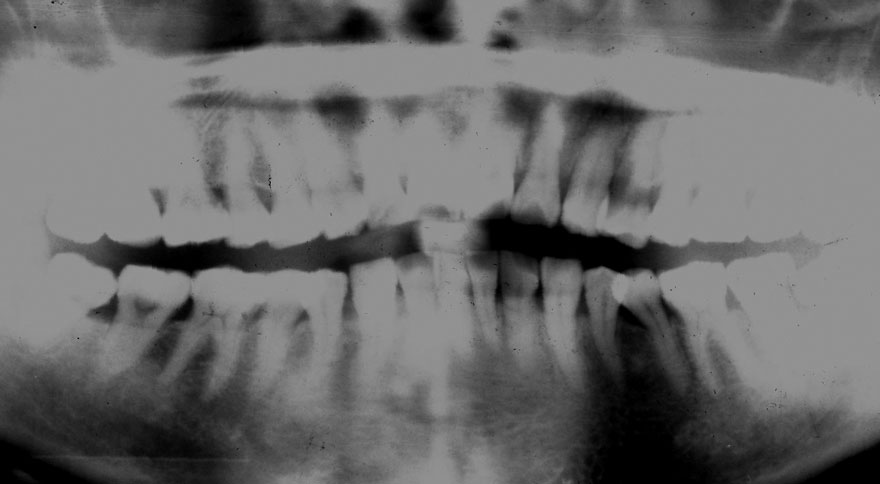

初診時 42歳 男性 平均歯槽骨喪失量:5.30mm

22年後 64歳

平均歯槽骨喪失量:5.554mm

22年間喪失量:-0.24mm

年間喪失速度:-0.01mm

(ケア頻度:1.07ヵ月ごと)